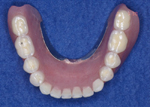

インプラント治療の症例(インプラント義歯)

55歳 女性

治療前

上顎、下顎ともにほとんど歯がのこっていません。

一般的な義歯を使っていましたが、固定されないため安定感がなく、会話や食事もしづらいようです。

治療中

下顎に残っていた歯を抜歯し、インプラント義歯の土台となるインプラントを四本埋入しました。

傷が治ったところで義歯を固定するためのパーツを装着していきます。

治療後

下顎の義歯がインプラント義歯です。

一見普通の総義歯のようですが、裏側に固定用の器具がついています。土台が装着されているため簡単に外れることがなく、また通常の総義歯よりも小型化され、違和感も少なくなります。